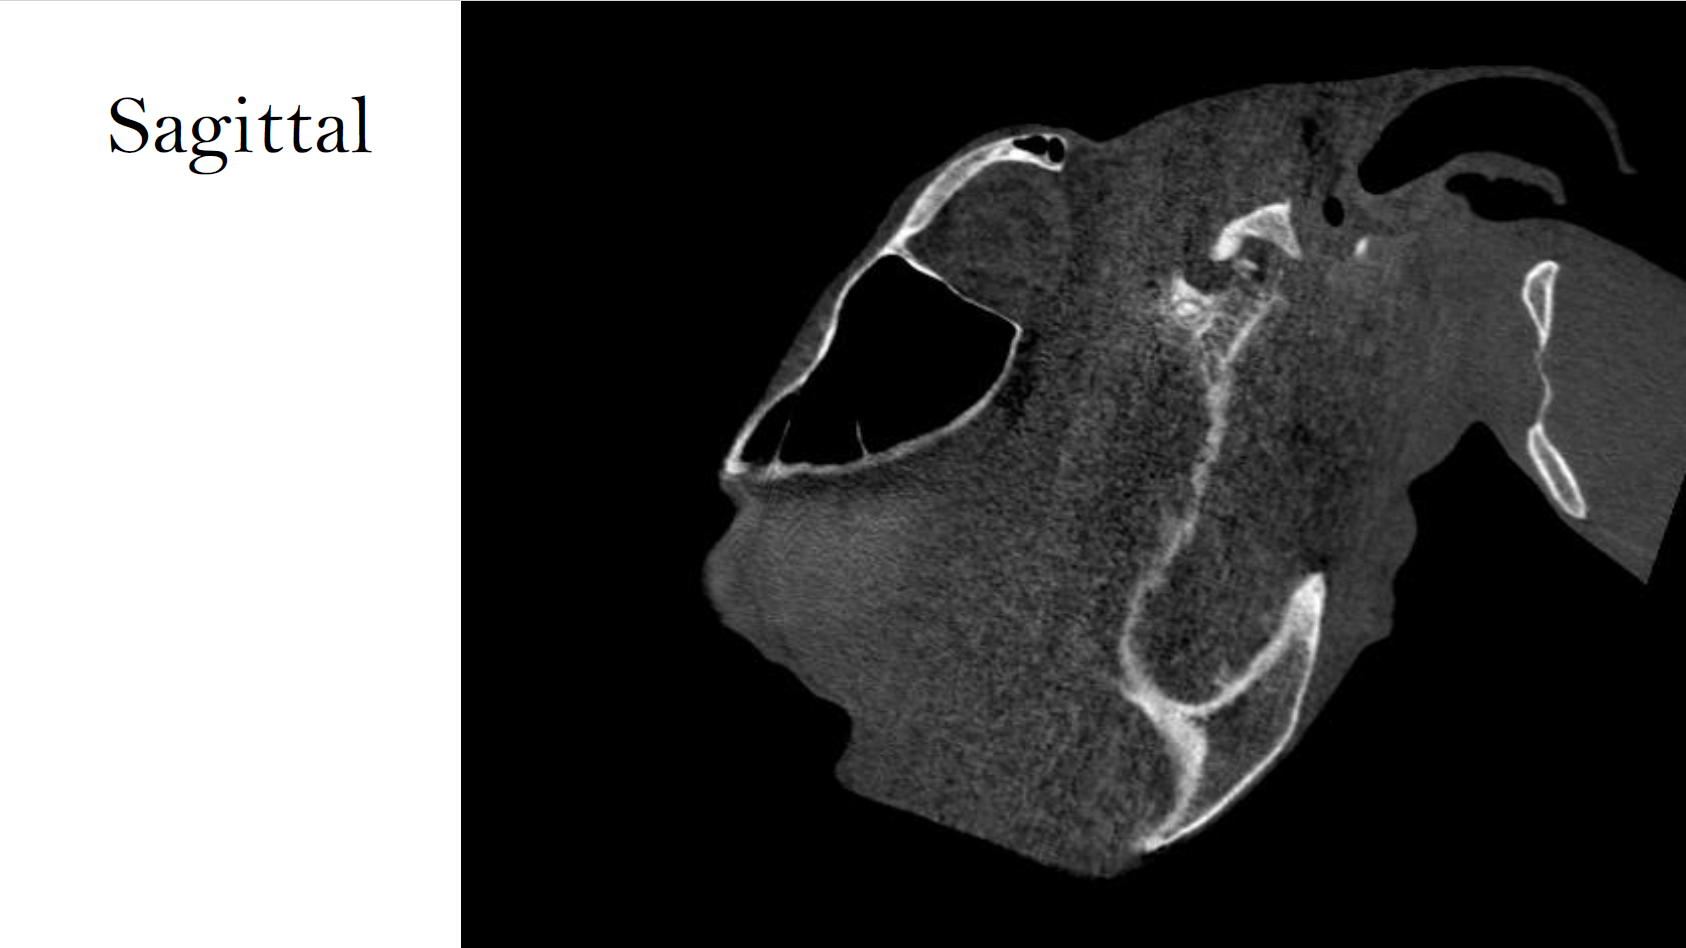

CT Findings:

• Severely comminuted acute (mildly) displaced closed and non-articular fracture of the ramus/neck of the left mandible. There was no radiographic evidence of luxation nor joint incongruency of the left temporomandibular joint.

• Small acute simple complete (mildly) displaced closed and non-articular fracture of the left paracondylar process.

• Faint hypoattenuating line though the left side of the cranium (parietal bone/zygomatic arch), DDx: vascular channel considered most likely, less likely fissure.

• Severe soft tissue swelling of the left side of the head (axial and abaxial), DDx: oedema, cellulitis, hemorrhage.

• Moderate to severe narrowing of the pharynx.

• Possible hematoma formation in the left guttural pouch, DDx: concurrent collapse due to abaxial soft tissue swelling.

CT enabled accurate localization and classification of fractures and soft tissue compromise, guiding treatment planning and airway monitoring.